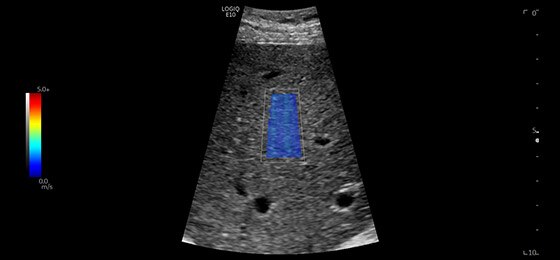

Liver Shear Wave Elastography, C1-6-D

2D Shear Wave Elastography quantifies tissue elasticity and provides color-coded elastograms.